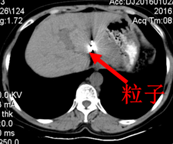

2015-10-26行CT定位下左肝占位碘125放射粒子植入术。

粒子植入术后2月CT: